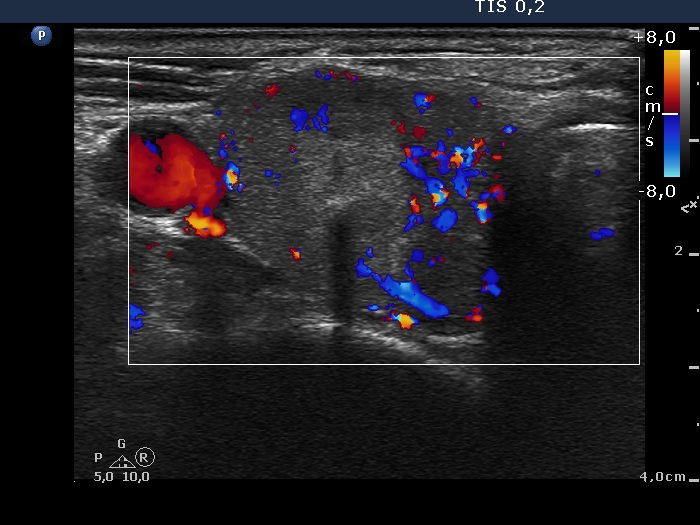

Ultrasonography: the thyroids were moderately hypoechogenic and contained several discrete, circumscribed lesions. There was a hyperechogenic nodule in the lower part of the right lobe while a cystic nodule in the upper part of the left lobe.

The thyroid is hypoechogenic and is surrounded with a relatively thin echonormal rim. This makes an appearance if both lobes were composed of a large hypoechogenic nodule. However, the echonormal rim corresponds to thickened connective tissue; a frequent phenomenon in an operated thyroid.

The upper part of the right lobe seems to be nodular, i.e. composed of two nodules at first sight. However, an insertion of the connective tissue and an acoustic shadow of a coarse calcification divides this part of the thyroid to two lesions. These do not fit nodules in a pathological sense.